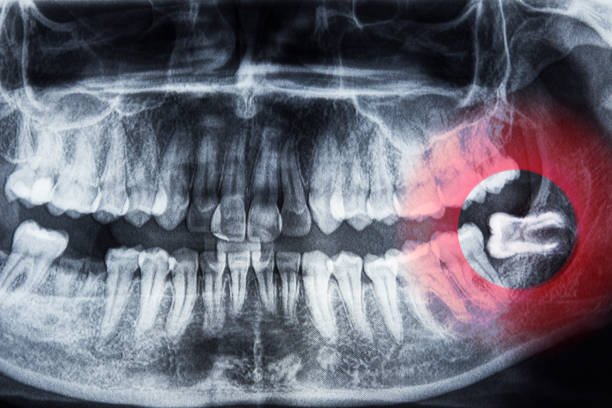

All About Wisdom Teeth: Your Go-to-Guide

Have you been entrusted with inquiries after your dental practitioner suggested that you remove your knowledge teeth?…